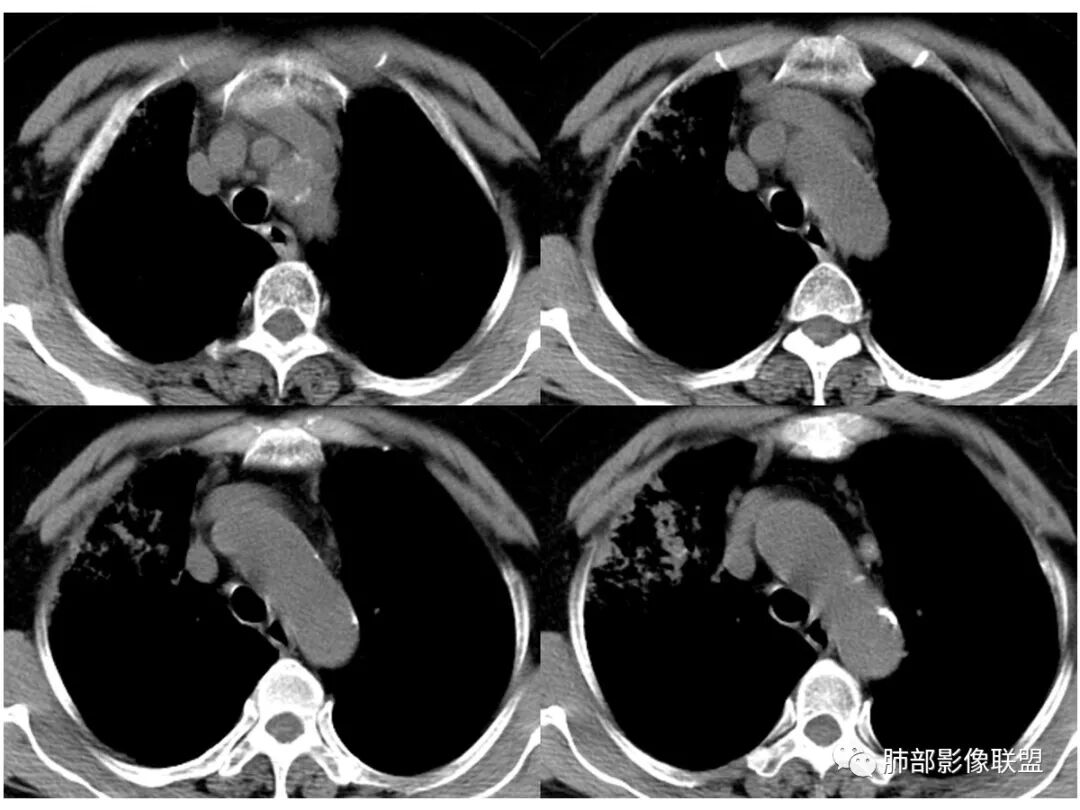

胸CT:右肺上叶实变内可见支气管充气征,近端支气管狭窄,远端扩张,周围可见毛玻璃影,右肺中叶支气管闭塞,并可见气道壁钙化,右肺中叶体积缩小,实变内可见空洞,并可见气液平面,空洞周围可见毛玻璃样影,右肺下叶支气管开口狭窄,右肺门淋巴结肿大。纵隔窗可见病灶与壁层胸膜间隙增宽,考虑良性病变-----感染性病变------TB?

右肺上叶病变,内见钙化及空洞,支气管可见,考虑结核伴出血。

右中叶支气管完全阻塞伴厚壁空洞,右上叶支气管不全阻塞伴大片GGN,右下部分GGN考虑腺鳞癌,结核待排。

老年女性,慢性病程,咳嗽伴白色粘液痰,无发热腹痛,糖尿病,白细胞及C反应蛋白不高,血沉快,铁蛋白高。胸部CT,右肺上叶大片状实变伴磨玻璃密度影,边界不清,边缘局部膨隆,叶裂弧形下坠,实变影宽基底与胸膜相贴;右肺下叶前基底段见类似病灶;右肺中叶不张并空洞形成,空洞内见气液平面;综合考虑右肺上叶及下叶肺炎型肺癌,右肺中叶结核。

这里是中叶的不张和空洞,有钙化,结核确实也不能排除

主病灶应该是粘腺腺癌,右中叶不张?,内空洞,壁光滑,考虑感染

纵隔窗,没有看到太多细支气管里粘液的密度。

中叶的体积缩小,也不是粘液腺癌能完全解释,